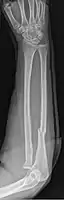

- Galeazzi fracture - not a fracture of the ulna but a displaced fracture of the radius accompanied by a dislocation of the ulna at the wrist, where the radius and ulna come together.[2]

Galeazzi facture (displaced fracture of the radius)